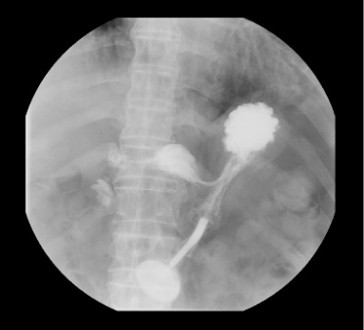

X線TV室

主に大腸内視鏡検査・消化器造影検査などを行っています。